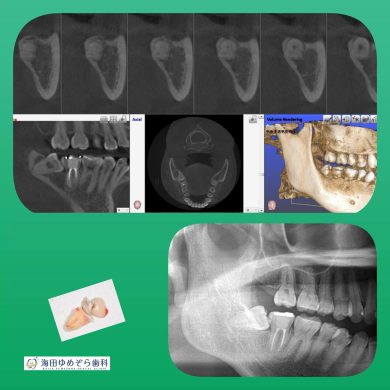

横向き親知らずの抜歯症例

院長はこのような横向きに埋まっている抜歯ケースも

1000症例以上の手術実績あり☆

横に埋まっている場合はCT撮影で安心です☆